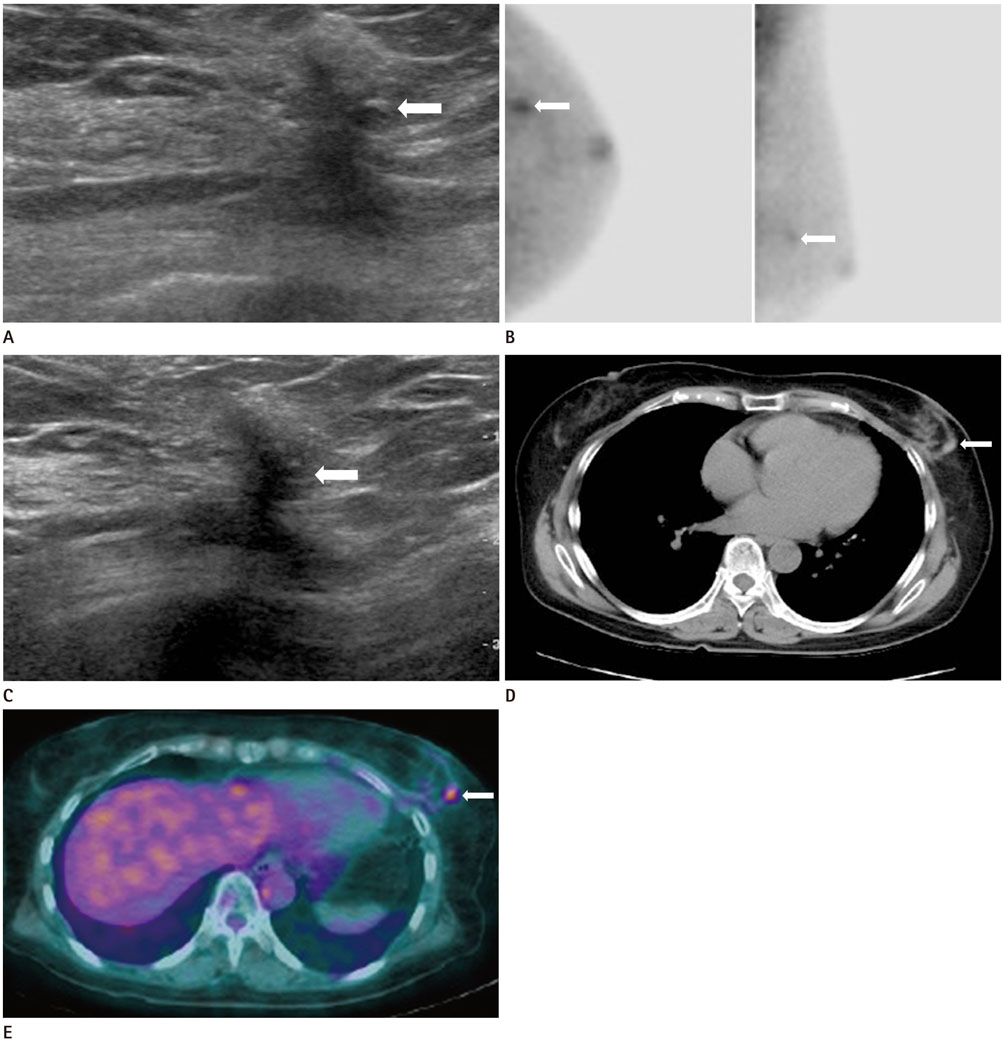

A Case of Recurrence-Mimicking Charcoal Granuloma in a Breast Cancer Patient: Ultrasound, CT, PET/CT and Breast-Specific Gamma Imaging Findings

- Charcoal remains stable without causing a foreign body reaction and it may be used for preoperative localization of a non-palpable breast mass. However, cases of post-charcoal-marking granuloma have only rarely been reported in the breast, and a charcoal granuloma can be misdiagnosed as malignancy. Herein, we report the ultrasound, computed tomography (CT), 18F-fluorodeoxyglucose-positron emission tomography/CT, and breast-specific gamma imaging findings of recurrence-mimicking charcoal granuloma after breast conserving surgery, following localization with charcoal in a breast cancer patient.